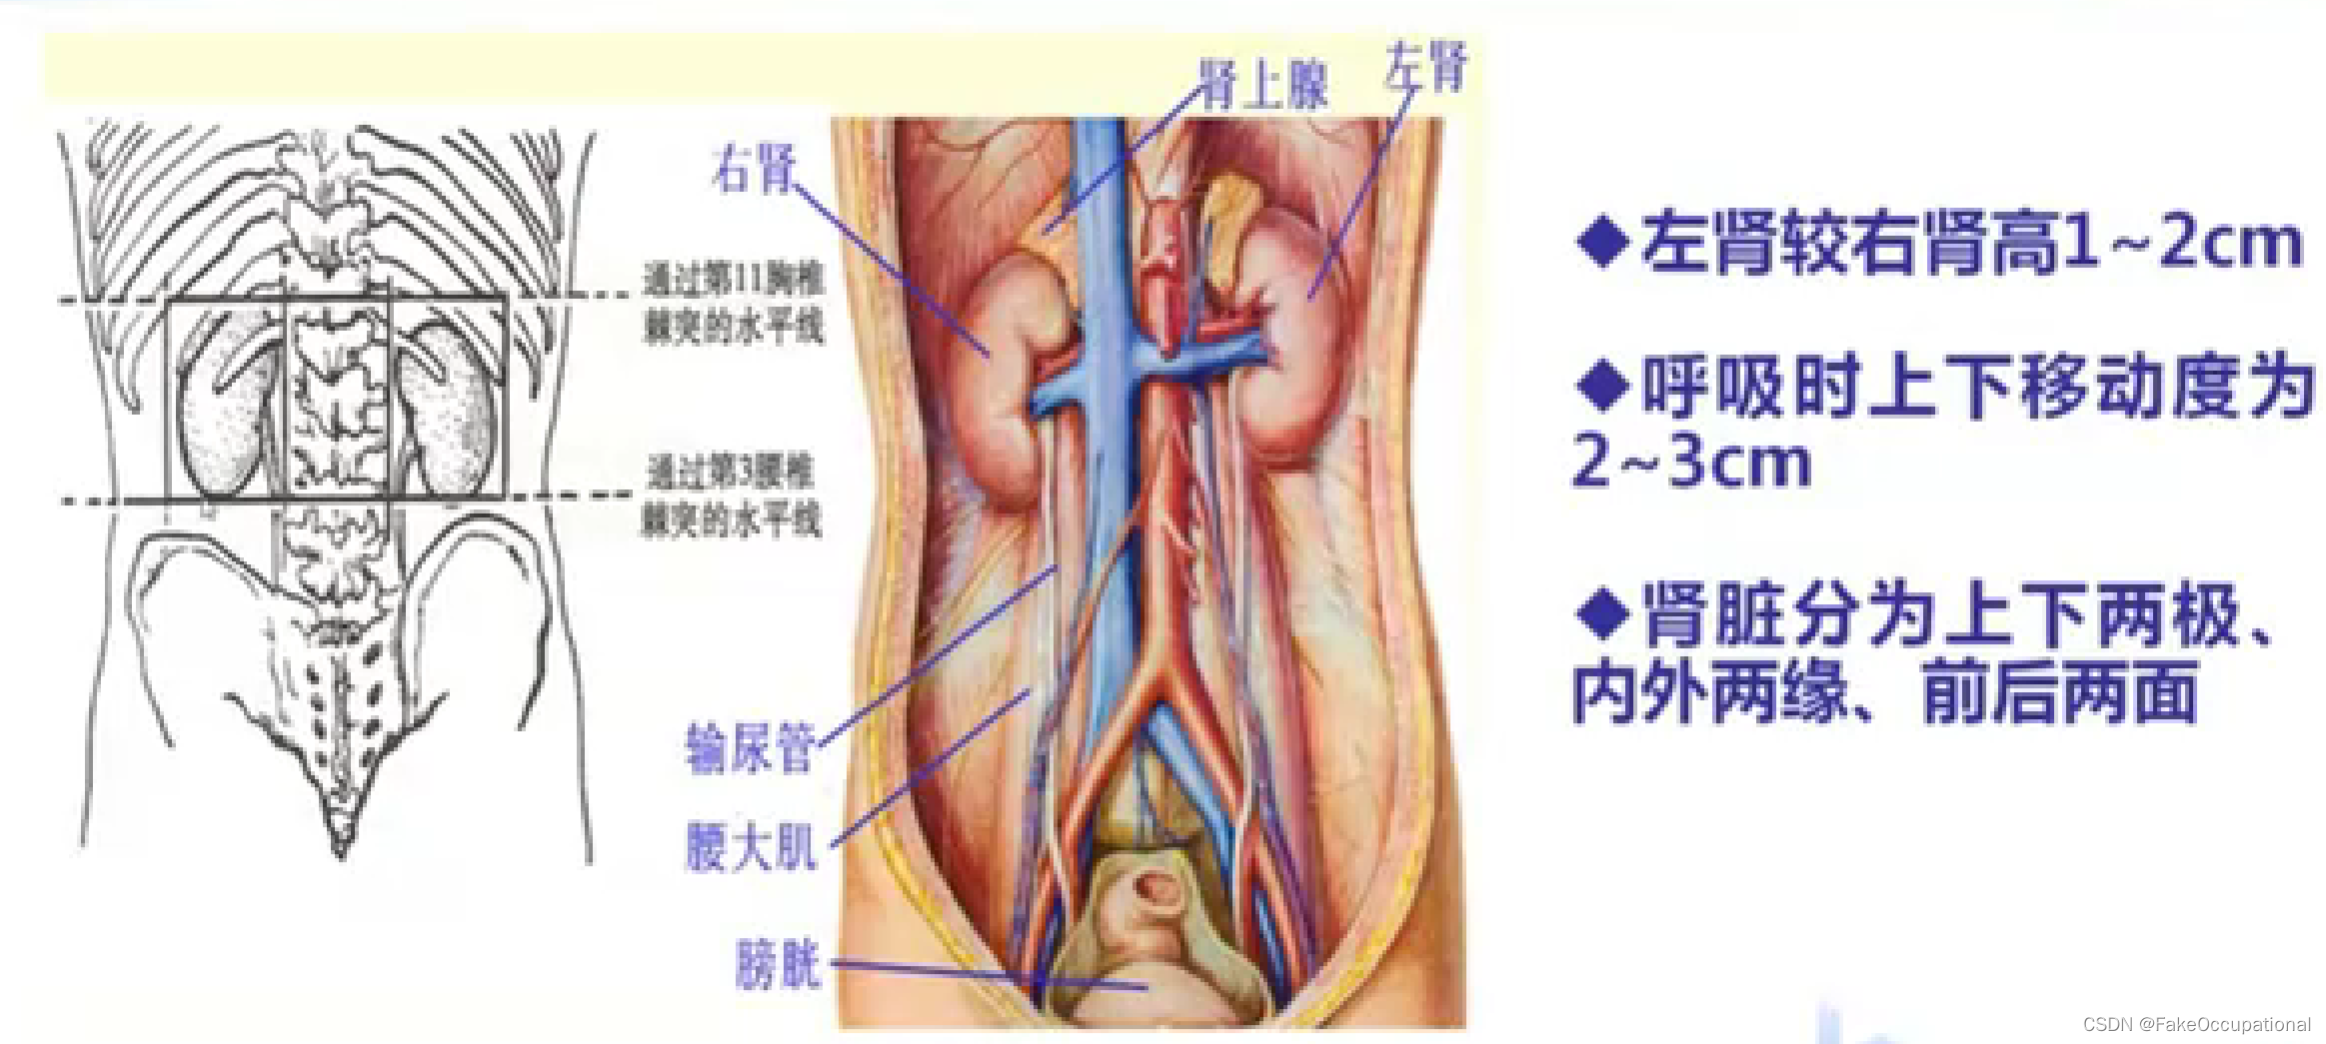

肾脏解剖概要